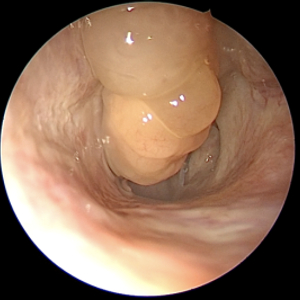

鼻息肉是长在鼻腔里的外表似荔枝肉样的光滑肿块,它并非肿瘤性新生物,而是鼻腔鼻窦过度炎症水肿的产物。单纯的鼻息肉较少见,常见的是慢性鼻-鼻窦炎伴有鼻息肉,且多发于双侧。

常常有人把下鼻甲(鼻腔的正常结构)误认为是鼻息肉,因为大家在照镜子时很容易观察到这个结构,而且发现有时候“这块肉”变红变大了,因此来院就诊。一般来说,观察鼻息肉需要借助医用工具,如前鼻镜或鼻内镜,否则很难被观察到。除非鼻息肉非常大、向前突出到鼻孔部位。

通过鼻内镜检查,刘教授观察到,陈先生上呼吸道双侧鼻腔中鼻道、嗅裂有鼻息肉,软腭平面和舌根平面没有明显狭窄。同时,鼻窦CT显示,陈先生患有双侧鼻窦炎。